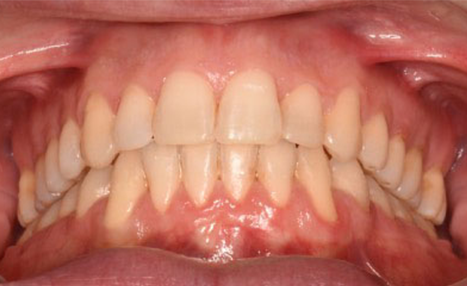

After 16 months of treatment, the transformation was evident:

(Image: 2 years after finishing)

This case demonstrates how precision in bracket placement and variable torque selection with Damon Ultima can fundamentally influence treatment efficiency and outcomes. By addressing torque control and smile arc from the very first appointment, round-tripping was minimized, biomechanics were optimized, and finishing required only fine adjustments rather than compensations.

The Damon Ultima system allowed the clinician to align facial esthetics, occlusal function, and long-term stability in a challenging adult case, underscoring the value of intentional planning and execution.